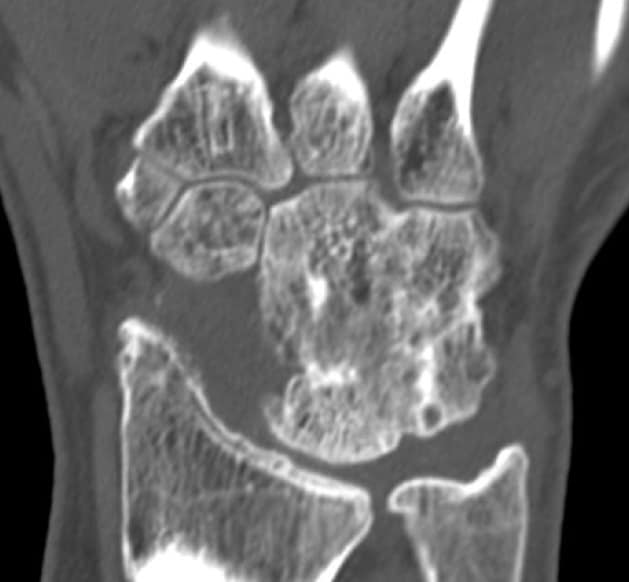

CT 1 Jahr postoperativ

Fusion ist vollständig durchbaut. Keine Osteolysen oder Resorptionszonen. Patient ist schmerzfrei.